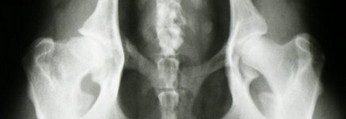

A - stawy biodrowe normalne

A - stawy biodrowe normalne.